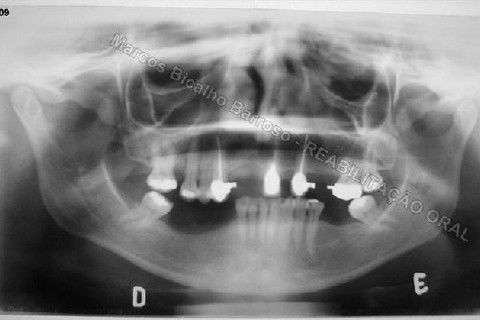

Paciente sexo feminino, 40 anos, queixava-se da situação da PPR superior, sem estabilidade, fraturas constantes nos dentes instalados. Sua vontade era resolver somente o problema da arcada superior, por questões financeiras. Logo no exame clínico inicial verifiquei a necessidade da reabiltiação inferior, pois este caso consistia em desarmonia oclusal severa, principalmente pela extrusão dos elementos 13,14 e 15 devido ausência de várias unidades inferiores. A proposta aceita pela paciente foi a instalação de 5 implantes na mandíbula + 5 implantes na maxila + tratamento endodôntico, osteoplastia e gengivoplastia nos dentes extruídos, incluindo núcleos metálicos e coroas em metalocerâmica (13,14,15). As coroas sobre implantes serão incialmente provisórias em resina fotopolimerizável e posteriormente metalocerâmica, de acordo com as possibilidades da paciente. Os procedimentos nos elementos extruídos serão apresentados em momento oportuno.